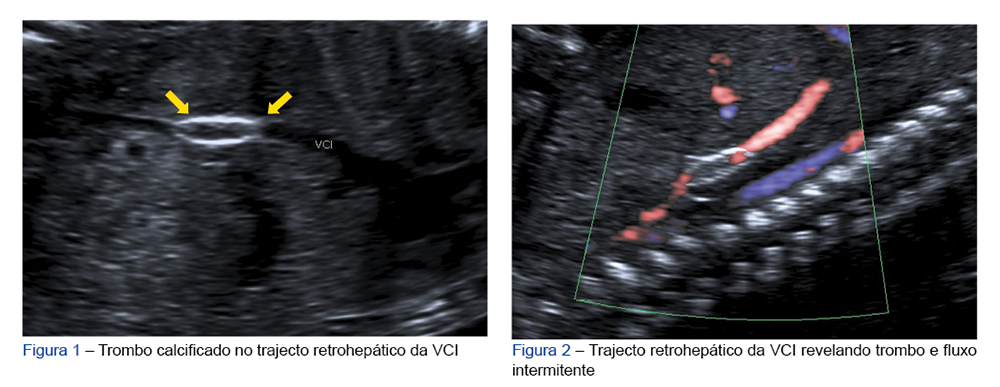

Diagnóstico Pré-Natal de Trombose da Veia Cava Inferior

Gestante de 37 anos, saudável, realizou ecografia morfológica que mostrou trombo calcificado de 10 x 3 mm no trajecto retrohepático da veia cava inferior (VCI) (Fig. 1) com fluxo intermitente (Fig. 2) e circulação colateral pela veia ázigos com vascularização renal normal. O estudo das trombofilias do casal foi negativo, tendo-se ainda excluído patologia hipertensiva, diabetes e infecção materna (incluindo a citomegalovírus), com vigilância posterior revelando estabilidade do trombo. O parto realizou-se às 38 semanas: recém-nascido masculino, 3715 gramas, índice de Apgar 9/10/10. O Doppler abdominal neonatal revelou VCI com imagem intraluminal calcificada bem como circulação colateral envolvendo o sistema ázigos, apresentando estudo das trombofilias normal.